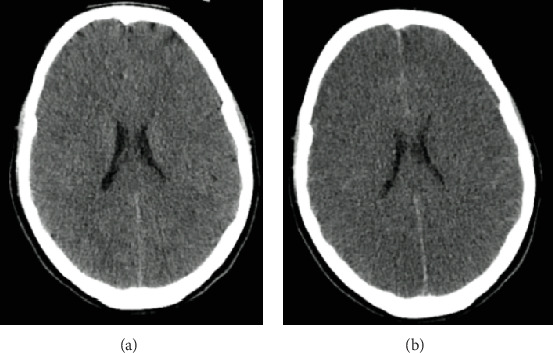

Abstract Image